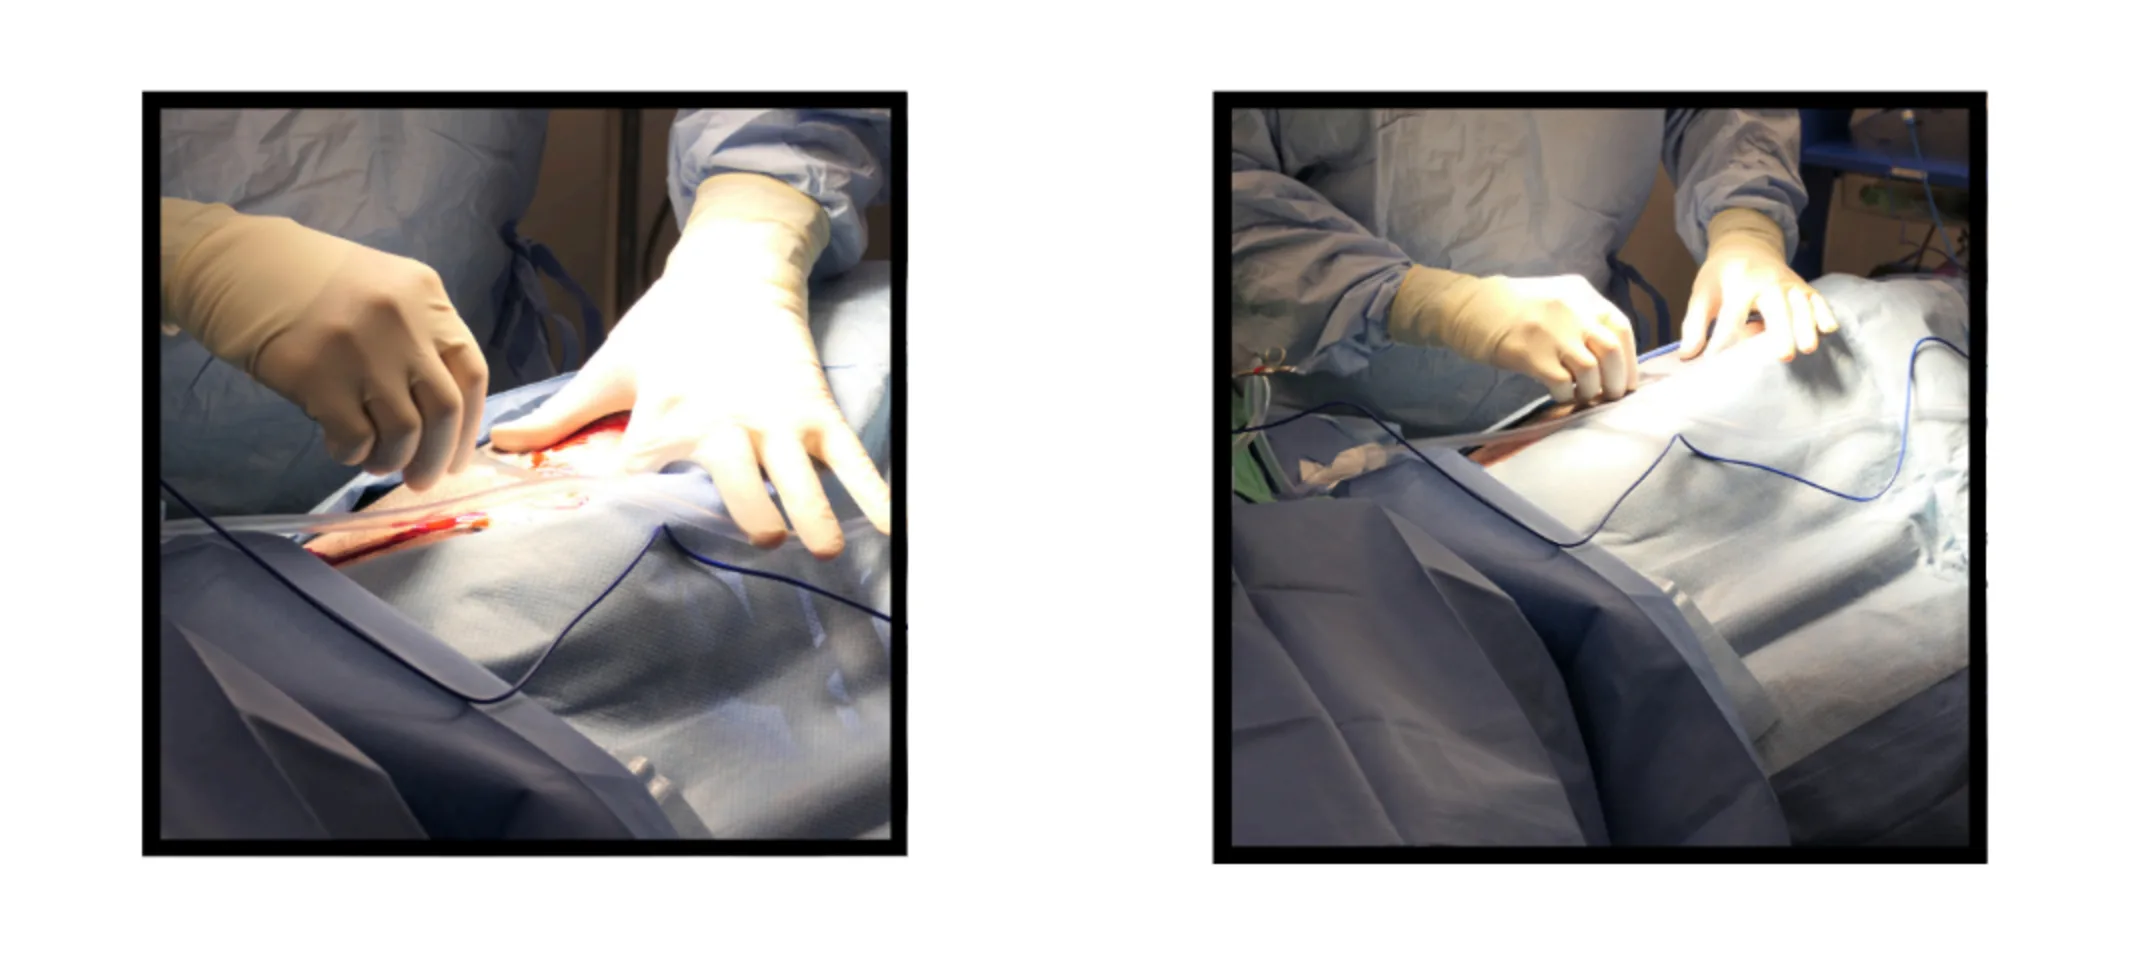

The surgery commenced with a precise ventral midline incision, extending from the xiphoid process to the caudal abdomen. This strategic approach provided optimal access to the affected organs and allowed for an efficient assessment and correction of the gastric torsion.

Upon opening the abdomen, Dr. Hillman identified the stomach in a typical GDV position, with the omentum unnaturally draped across the front. With expert care, the stomach was gently maneuvered back into its correct anatomical position. An orogastric tube was then inserted to decompress the stomach, relieving the built-up pressure and mitigating the risk of further vascular compromise.

Notably, the surgery also revealed significant damage to the spleen, marked by darkened, congested tissues indicative of hemorrhage. This necessitated a splenectomy, performed to ensure complete removal of the spleen while preserving surrounding structures.

Following the successful repositioning and stabilization of the stomach, an incisional gastropexy was executed. This procedure involved suturing the stomach wall to the abdominal wall to prevent future occurrences of torsion—a preventative measure crucial for GDV-prone breeds like Bernese Mountain Dogs.

The closure of the surgical sites was performed with equal precision, using layers of sutures that would promote optimal healing while minimizing discomfort.